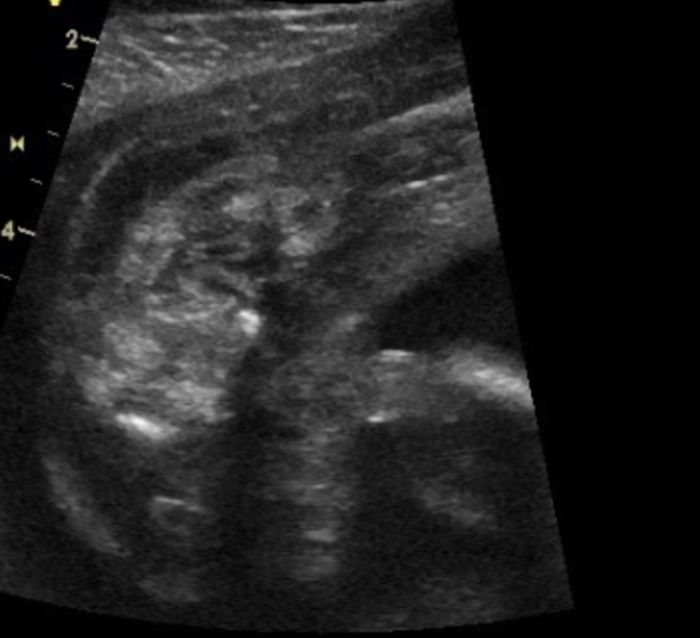

Já myslím, že to je holčička. Vidím kávové zrno jestli je to ono

Mě fascinuje, jak to někdo z těhle šmouh dokáže rozeznat

. Já nevidím nic, jen fleky

Holčička..

Kluk